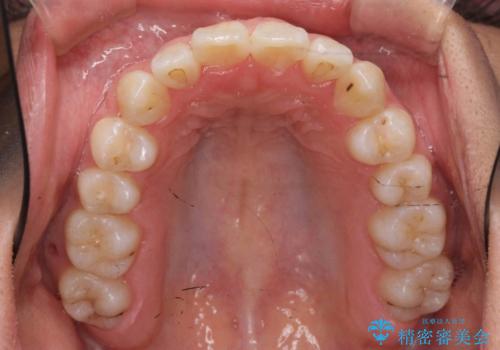

リファインメントもなく、1回で治療が終了しました。大変うまくいったケースです。

主治医としては、前歯の並びをもう少しこだわりたかったのですが、満足度が高く、リファインメントは希望されませんでした。

抜歯をしていないので口元は変わっていません。

八重歯も重症でなければインビザラインでも並びを歯を抜かずに整えることができます。